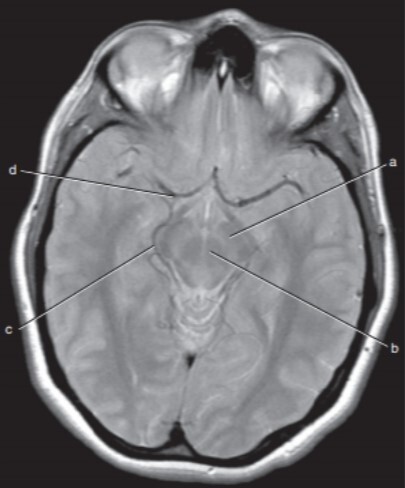

Label a,c,d

a=Left cerebral peduncle (of Midbrain)

c=Right ambient cistern (with Rt posterior cerebral artery)

d=Right middle cerebral artery

Label a,b,c,d,f,g

a-Rt lateral fissure

b=Insula

c=Quadrigeminal cistern

d-3rd ventricle

f-Cerebellum

g=Anterior horn (of rt lateral ventricle)